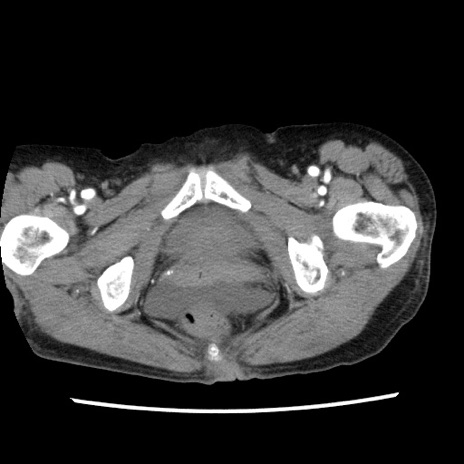

矢状断像

【症例】80歳代女性

【主訴】腹痛

【現病歴】8時間前から腹痛あり来院。

【既往歴】糖尿病、脂質異常症、子宮体癌にて子宮全摘術

【身体所見】意識清明・会話良好だが腹痛で苦悶様、全腹部にわたって反跳痛と圧痛あり

【データ】WBC 13600、CRP 0.14、LDH 224、CK 90